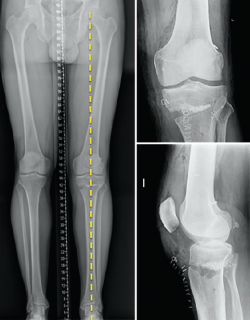

One of the aspects often not adequately taken into account when considering the surgical management of knee instability is the influence of the loading axes upon the instability itself. A varus morphotype or axis associated to anterior instability due to ACL deficit tends to be the most frequent combination.

[[{"fid":"4714","view_mode":"default","fields":{"format":"default","alignment":""},"type":"media","field_deltas":{"5":{"format":"default","alignment":""}},"link_text":null,"attributes":{"class":"media-element file-default","data-delta":"5"}}]]

Effect of varus deformity upon the anterior cruciate ligament

Different studies have shown that deformity of the coronal axis in varus considerably increases loading upon the ACL(40). Mechanical varus of 10º implies an overload of over 400% upon the ACL at 30º of knee flexion or 100% in extension. Minor deviations of the neutral mechanical axis, even slightly above "physiological" varus, such as 5º, already imply an increase in stress upon the ACL (250% at 30º and 68% in extension).

In addition, mention must be made of the high prevalence of meniscal damage associated to ACL lesions(41,42), due to simultaneous damage to both structures, or as a consequence of stress secondary to the instability. Therefore, the combination of varus and anterior instability defines a harmful pattern requiring the consideration of single-step resolution of both situations when marked varus is associated to anterior instability(43).

We should bear in mind that although the indication of osteotomy resides in varus correction (coronal plane), the osteotomy will also affect the sagittal and axial planes (Figure 5).